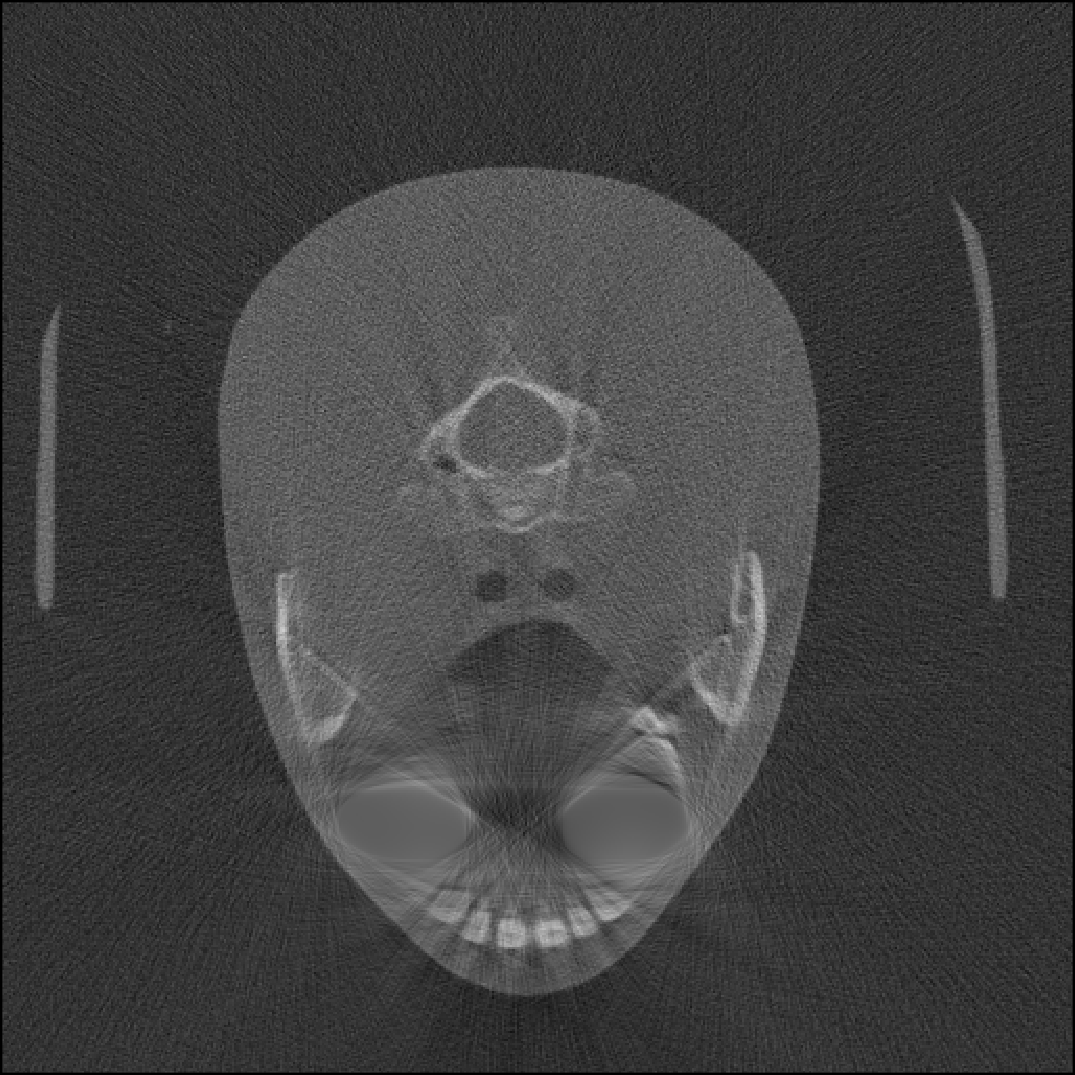

In practice, the complex wavelet transform is an effective tool for extracting singularities from a signal, as previously demonstrated for CT wavefront set extraction in [39]. In images and volumetric data, large-magnitude wavelet coefficients typically occur near jumps and edges. See Fig. 1 for an example of a sinogram containing two metal inserts, where the sum of the absolute values of the wavelet coefficients reveals the corresponding metal boundaries.

We propose a MAR method for projection-domain metal segmentation and inpainting, that uses 3D DT-CWT to find the edges of metals in the 3D sinogram. Fig. 2 shows the full workflow from 3D sinogram to metal artifact reduced reconstruction. The method is explained in detail below.

4.2 Binary mask for metal segmentation

To move from the complex wavelet coefficient space to the 3D sinogram space , we take a sum over the absolute value of the thresholded coefficients:

| (9) |

revealing the locations in the 3D sinogram space corresponding to the largest coefficients. See the 2nd row of Fig. 3 for an illustration of the resulting point cloud for two different 3D sinograms. Then, the result is binarized to by:

| (10) |

where denotes the indicator function.

As mentioned in the previous subsection, the binary point cloud might still have voxels that are not related to a true metal trace, due to superimposition of features in the 3D sinogram. To remove these residuals, we leverage the geometric structure of sinograms and discard isolated voxels that do not align along a continuous geometric trajectory in the -direction. That is, a voxel is retained only if it has nonzero support within an -neighbourhood in the plane in at least neighbouring slices along the -direction, within a prescribed depth :

| (11) | ||||

with neighbourhood

Voxels that fail this connectivity test are removed as isolated noise. By iterating this procedure, the remaining structures exhibit coherent propagation across slices, resembling the flow of information in a CBCT sinogram. The resulting values form a point cloud that corresponds to the singular support of the metal traces in the 3D sinogram space.

Next, we convert , which contains points located on metal boundaries, into a full binary mask for metal segmentation. Since the extracted boundary may not form a closed surface, we complete it using standard morphological operations [21]. In particular, we apply morphological closing, which consists of a dilation followed by an erosion using the same structuring element .

After the boundary has been closed, the interior is filled using a flood-fill operation (MATLAB’s ’imfill’ function). The resulting binary mask represents the segmented metal regions in the 3D sinogram (see the third row of Fig. 3).

4.3 Sinogram inpainting and metal-free reconstruction

Using the metal mask , voxels corresponding to metal structures are segmented from the original 3D sinogram , yielding a metal-removed sinogram . See the fourth row of Fig. 3. The missing regions are filled using harmonic inpainting by solving the discrete Laplace equation within the masked region subject to Dirichlet boundary conditions prescribed by the surrounding known pixel values using MATLAB’s ’regionfill’ function.